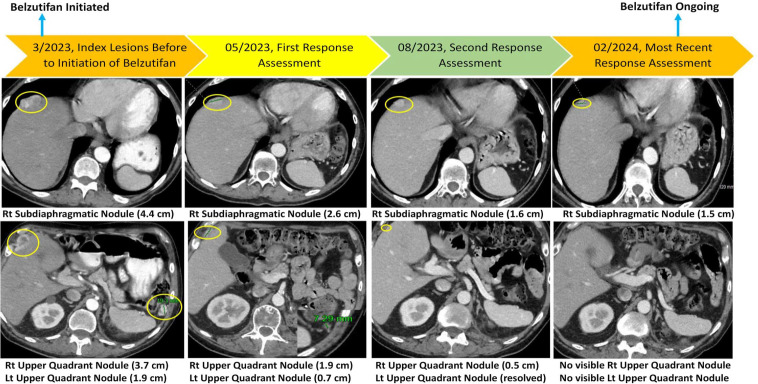

Clear cell renal cell carcinoma (RCC) is commonly associated with alterations in the VHL tumor suppressor gene, resulting in upregulation of hypoxia-inducible factor pathways. Immune checkpoint inhibitors and vascular endothelial growth factor inhibitors are the mainstays of systemic treatment for metastatic RCC; however, most patients encounter disease progression after the initial response. The phase 3 clinical trial LITESPARK-005-belzutifan (HIF-2α inhibitor) demonstrated improvement in progression-free survival compared with everolimus in heavily pretreated patients unselected for somatic/germline VHL alterations (an objective response rate of 23% and a median time on therapy of 7.6 months in the belzutifan cohort), resulting in U.S. FDA approval for patients with advanced RCC. Herein, we present two cases of refractory metastatic RCC (including one with brain metastases) with somatic VHL mutations who received belzutifan after discussion in the institutional Molecular Tumor Board. Both patients had an excellent clinical response (partial remissions ongoing at >12 and >20 months). Future studies should assess the merits of biomarker selection for belzutifan treatment.